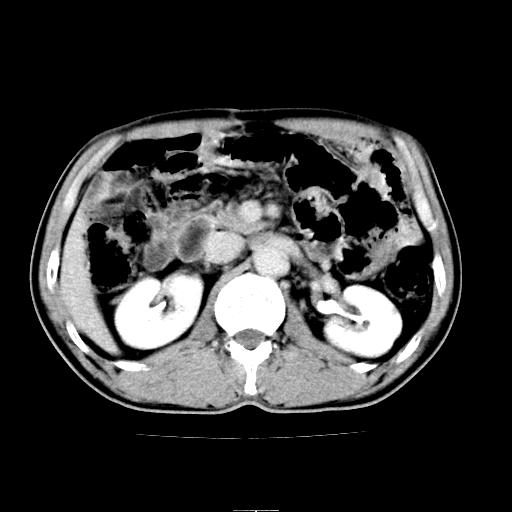

患者男,64岁,胃癌术后三个月,无明显不适。请讨论一下胰头前方小圆形低密度影为淋巴结还是肠管?

肠管吧.另外右肾见盂旁囊肿.

肠管.右肾见盂旁囊肿.

胰头低密度影考虑是肠管

应该考虑是肠管,理由1、平扫和增强对比,形态和内部的密度有明显改变。2、增强图片可见明显气液平面。

是肠管影,肠壁有强化。

支持肠管

是肠管,右肾低密度灶形态不规则、密度不均匀,不除外转移.

是肠管影。还有右侧肾盂旁囊肿。